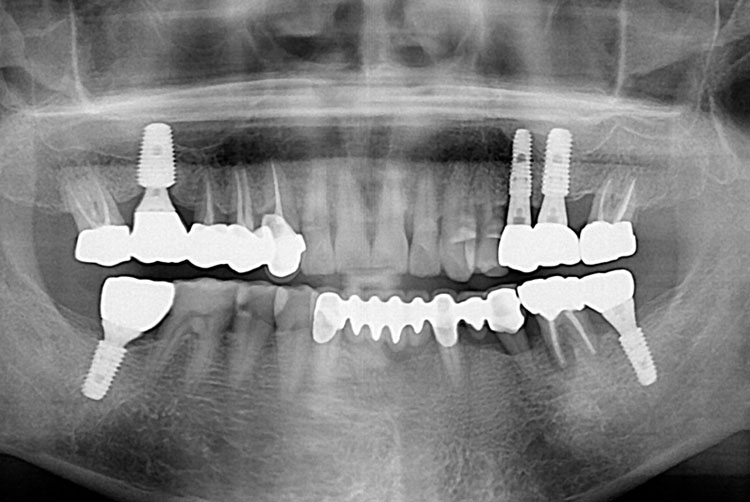

[임플란트] 임플란트

치료전 : 2018-06-20

세종치과는 많은 환자와 다양한 케이스를 바탕으로 항상 편안한 임플란트 수술을 제공하고자 노력하고,

오래동안 튼튼히 쓸 수 있는 임플란트 수술을 가장 큰 목표로 삼고 있습니다.